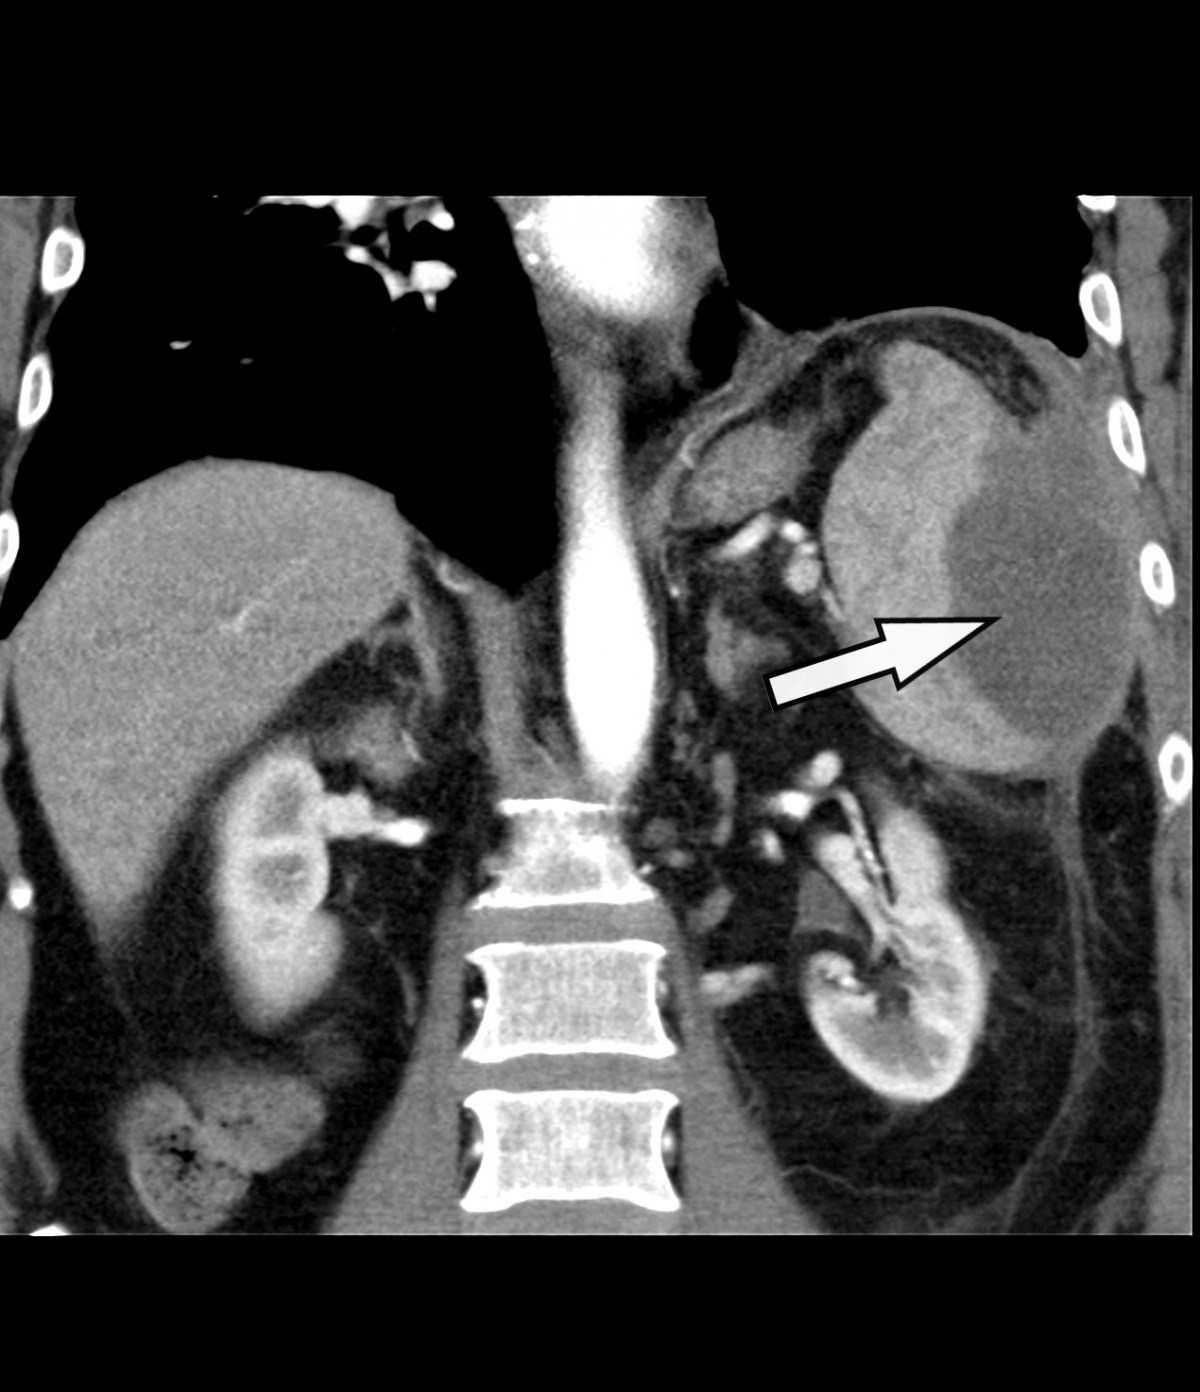

(7 Tage nach Drainageneinlage)

zeigt sich bei unverändert

regelgerecht einliegender

Drainage (Pfeil) der Abszess vollständig entleert.

In einer abschließenden CT (7 Tage nach Drainageeinlage) bestätigte sich die vollständige Entleerung und Kollabierung der Abszesshöhle (Abbildung 4). Somit konnte eine erfolgreiche definitive Behandlung des Milzabszesses konstatiert und die Drainage entfernt werden. Die Indikation zur Befundkontrolle mittels CT wurde gestellt, da der subphrenische Raum sonografisch oft schwierig und nur unzureichend einsehbar ist.